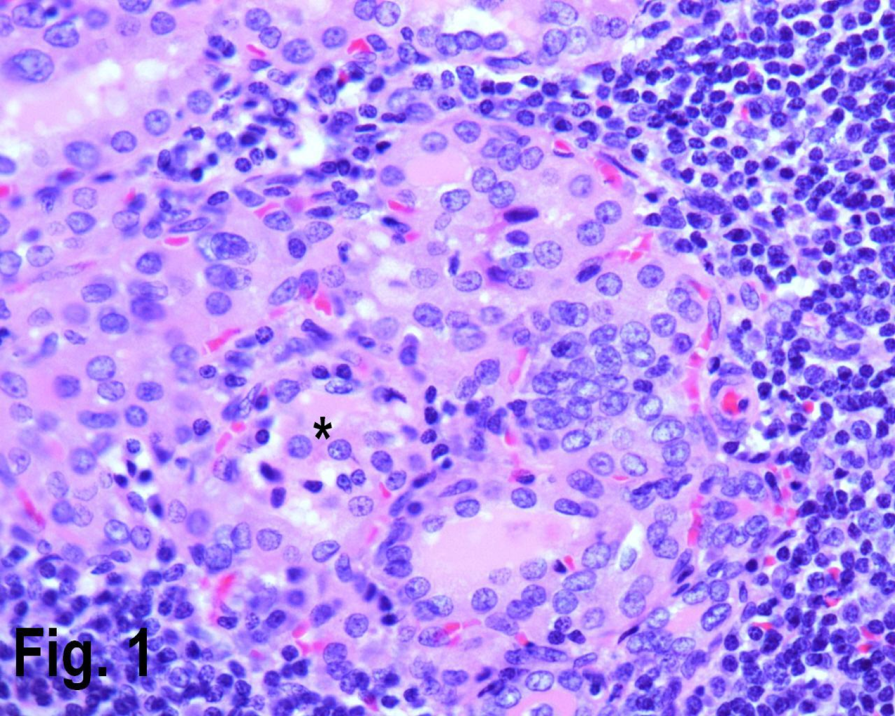

Total number of thyroidectomies performed in our institution over a nine years period was 256, of which 171 cases were non neoplastic, 85 neoplastic; of those 23 cases were adenomas and 62 cases were malignant (Table 1). The non neoplastic lesions (multi nodular goiter and auto immune thyroiditis) peak frequency was in third to fifth decades (Table 2). The youngest patient in our series was twelve years male with colloid nodule. The age ranged from 12 years to 78 years. Of the total non neoplastic lesions, there were 142 females constituting 80% in this series and the male to female ratio was 4:1. Female accounted for 99 cases (80%) of the multi nodular goiter, 14 cases (93%) of goiter and thyroiditis, 20 cases (95.2%) of Hashimoto’s thyroiditis (Figure 1) and 8 cases (80%) of colloid nodule.

Figure 1.High power view showing Hashimoto’s thyroiditis with lymphocytic infiltrate in the periphery and Hurthle cells {asterisk} in the center. (Hematoxylin & eosin, original magnification ×400).